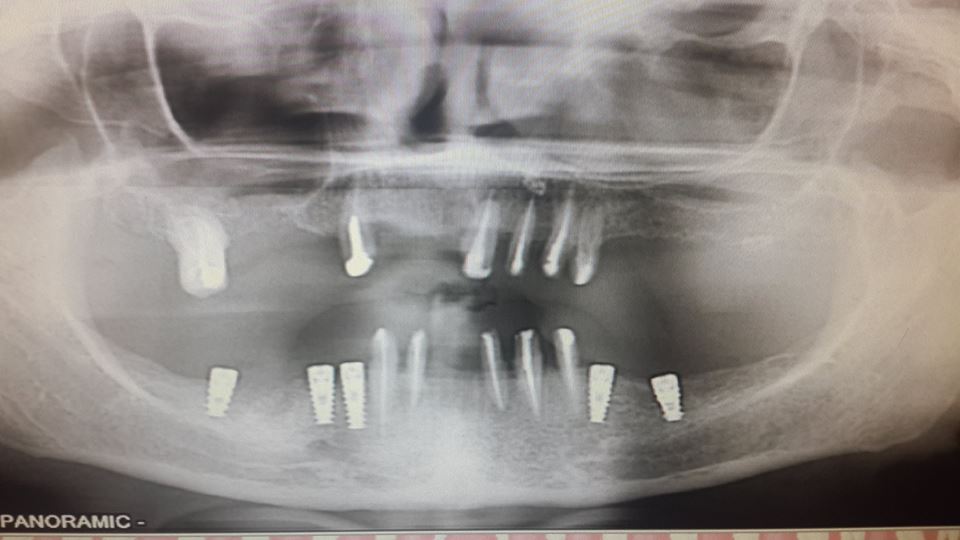

An example of complete rehabilitation of the oral cavity. Treatment included the removal of the old prosthesis, treatment of paradontitis, removal of a large cyst, implantation, clasp prosthesis.